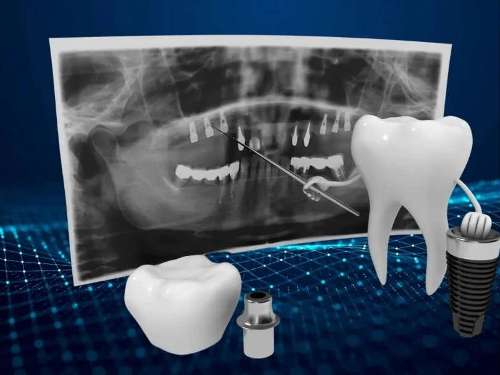

With advancements in implant materials and techniques, dental implants are now more comfortable and durable than ever before. Gone are the days of uncomfortable dentures or bridges that can slip or cause discomfort. Dental implants mimic the look and feel of natural teeth, allowing you to eat, speak, and smile with confidence.